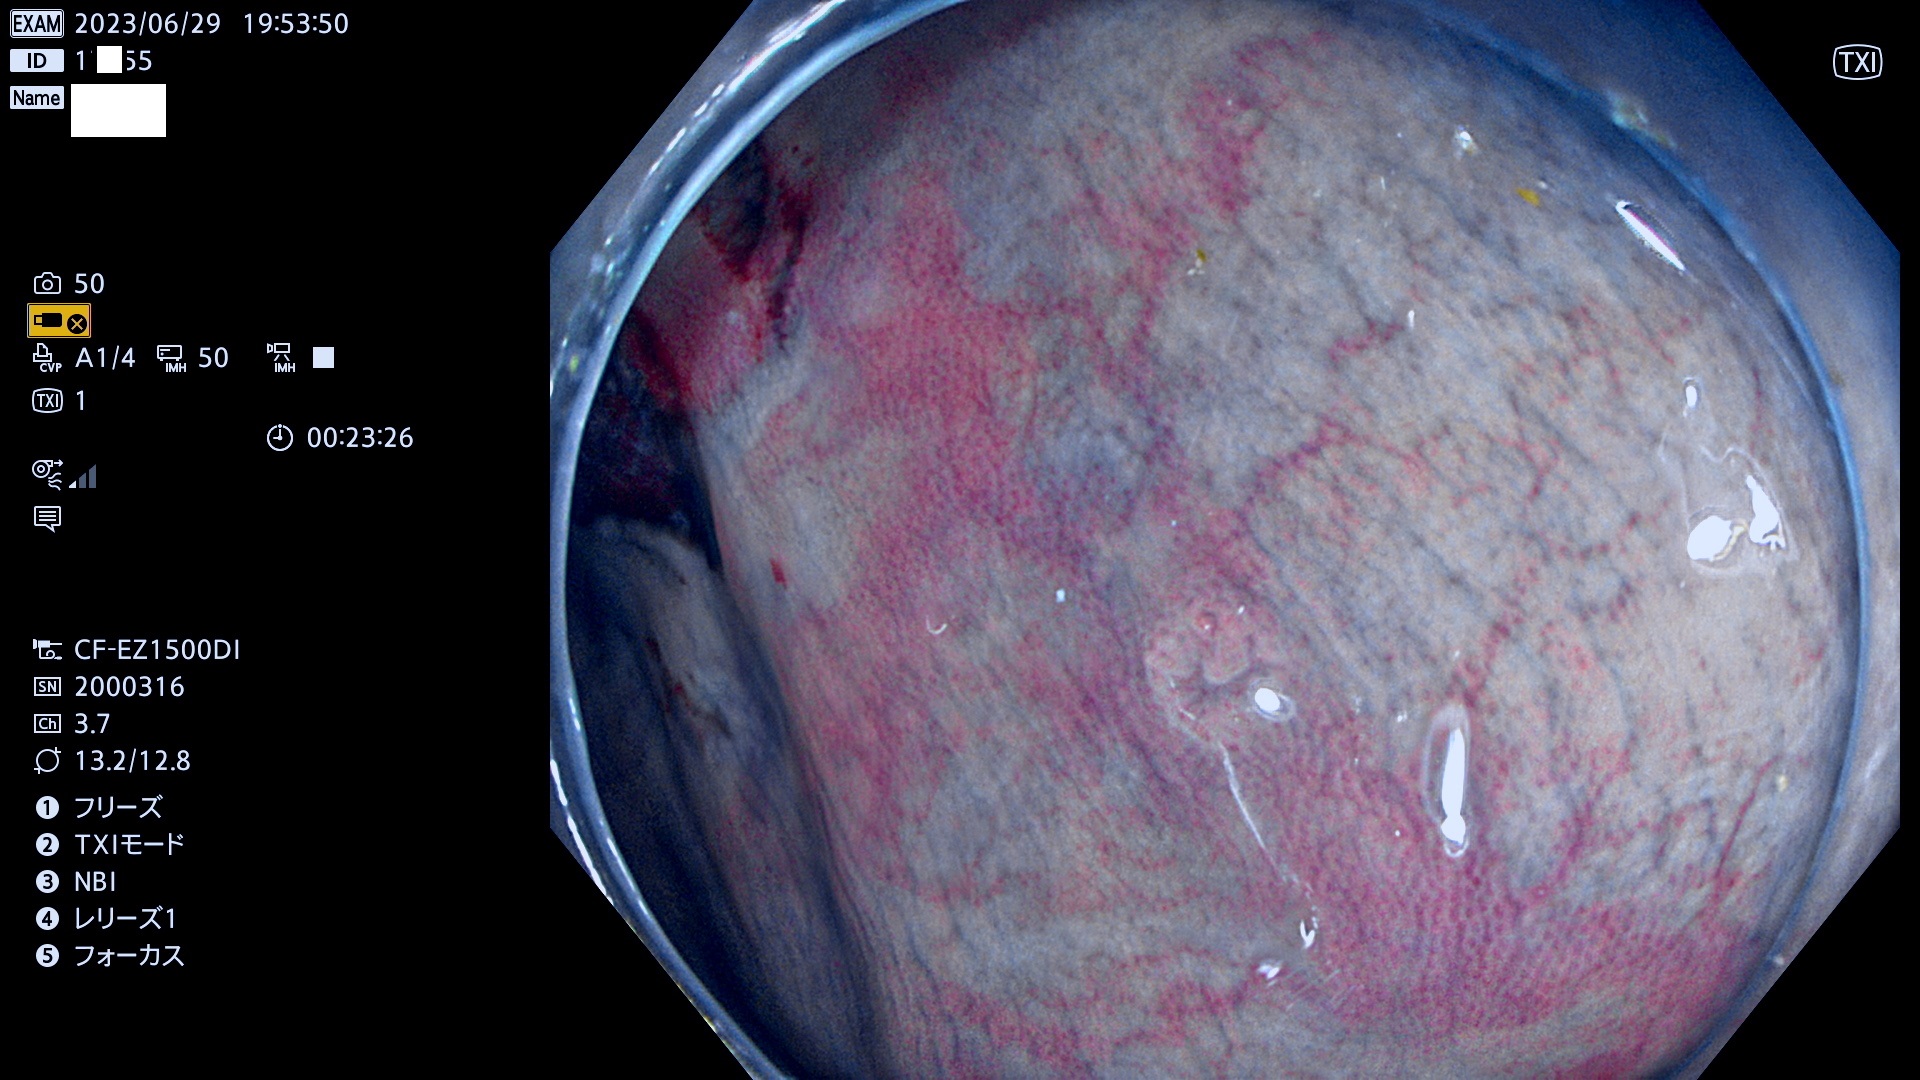

「表面型腫瘍」の中で、完全に平坦な物をUb、陥凹している物をUcと呼びます。平坦隆起型(Ua)よりも、発見が難しく危険な病変です。このタイプの発見率は「腺腫発見率」よりも、遥かに重要な意義があります。

抽出の対象期間 2023年6月29日(木)〜7月2(日)の4日間(48件の検査)8件